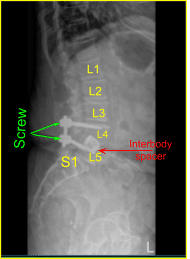

Dada la preocupación por el implante en decúbito prono y nuestra sensación de que las placas terminales pueden haberse fracturado más, expusimos los procesos transversales para L4 y L5 y utilizamos el taladro para crear orificios piloto en el pedículo en el lado izquierdo en L4 y L5. Bajo fluoroscopia, guiamos las sondas a través de los pedículos y golpeamos cada pedículo, luego colocamos tornillos pediculares en L4 y L5.

Estos tornillos fueron estimulados y revisados bajo fluoroscopia, y luego se colocó un montado y se apretaron los tornillos de la tapa. En el lado derecho e izquierdo, decorticamos las facetas y los procesos transversales y colocamos nuestra masa de fusión para la artrodesis.